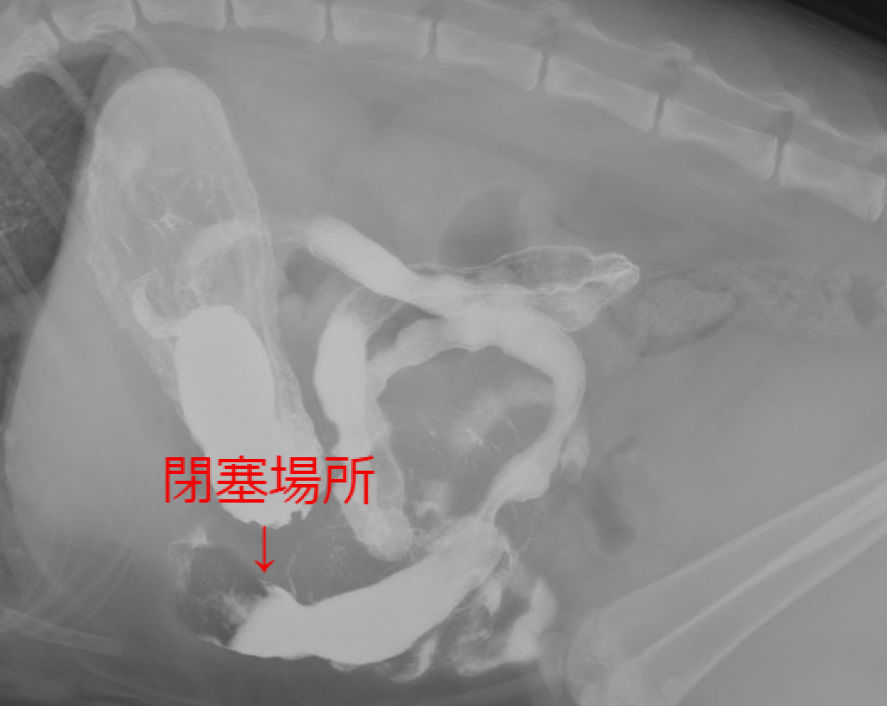

ネコの消化器型リンパ腫の外科手術(腫瘍外科) やまと動物病院 - 猫 腸閉塞 症状

ネコの消化器型リンパ腫の外科手術(腫瘍外科) やまと動物病院